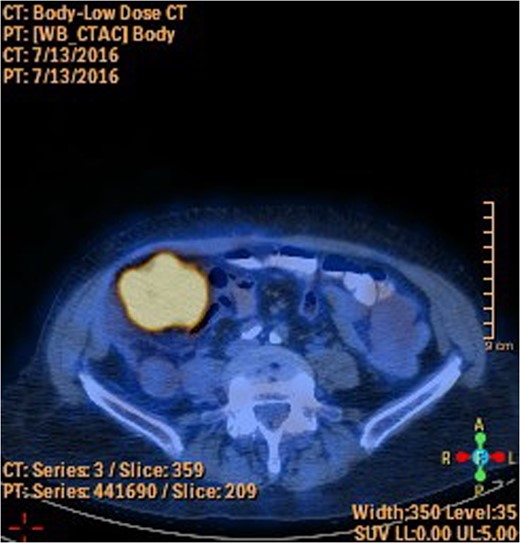

A 78-year-old female presented with worsening abdominal pain over 1 week, with onset of symptoms occurring 3 months prior. No history of recurrent fever or weight loss was elicited. There were no changes in bowel habits and she denied melena or hematochezia. She endorsed a normal colonoscopy three years prior. Of note, she was diagnosed with a biopsy proven squamous cell cancer of her left lower lobe 4 months earlier (Fig. 1). A PET scan performed just three weeks prior to her presentation demonstrated significant FDG uptake in the left lower lobe as well as the cecum, with no convincing evidence of regional nodal disease in the lungs (Figs 2 and 3).

The importance of establishing the right diagnosis is exemplified in our case. Our patient was referred to a thoracic surgeon for consideration of oncologic resection of her primary lesion. While the presence of a colonic primary certainly influences the decision regarding management, the presence of metastatic disease to the GI tract negates curative resection and portends a poor prognosis. Of note, our patient demonstrated isolated colonic metastasis in the absence of regional nodal disease on PET-CT. The sensitivity of PET-CT in detecting mediastinal disease has been shown to be as low as 78%, likely influenced by a multitude of factors including tumor biology [6]. As such, an area of distant FDG-avid activity should be presumed to represent metastatic disease, even in the absence of regional or mediastinal disease, until proven otherwise.